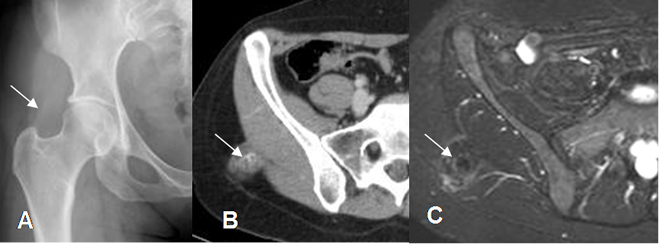

La apariencia con la RM, depende del tiempo de evolución. En las fases iniciales es similar a otra lesión muscular y en las tardías existe edema muscular, rodeando las imágenes hipointensas, que corresponden a calcio o fibrosis densa. (2). (Fig 31 y 32).

Fig 31. Miositis osificante.

A: Rx AP. Incipiente calcificación en sentido oblicuo, sobre la región glútea derecha.

B: TAC axial y C: RM axial en STIR. Prominencia de tejidos blandos en relación con el músculo glúteo. Hay área densa en el TAC e hipointensa en la RM, que corresponde a calcificación, por miositis osificante.